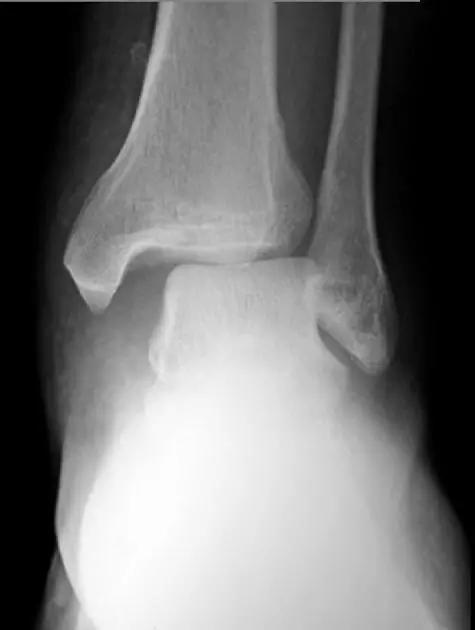

5. Maisonneuve 骨折

腓骨近端骨折伴内踝骨折及三角韧带断裂。

(来源:Radiopaedia)